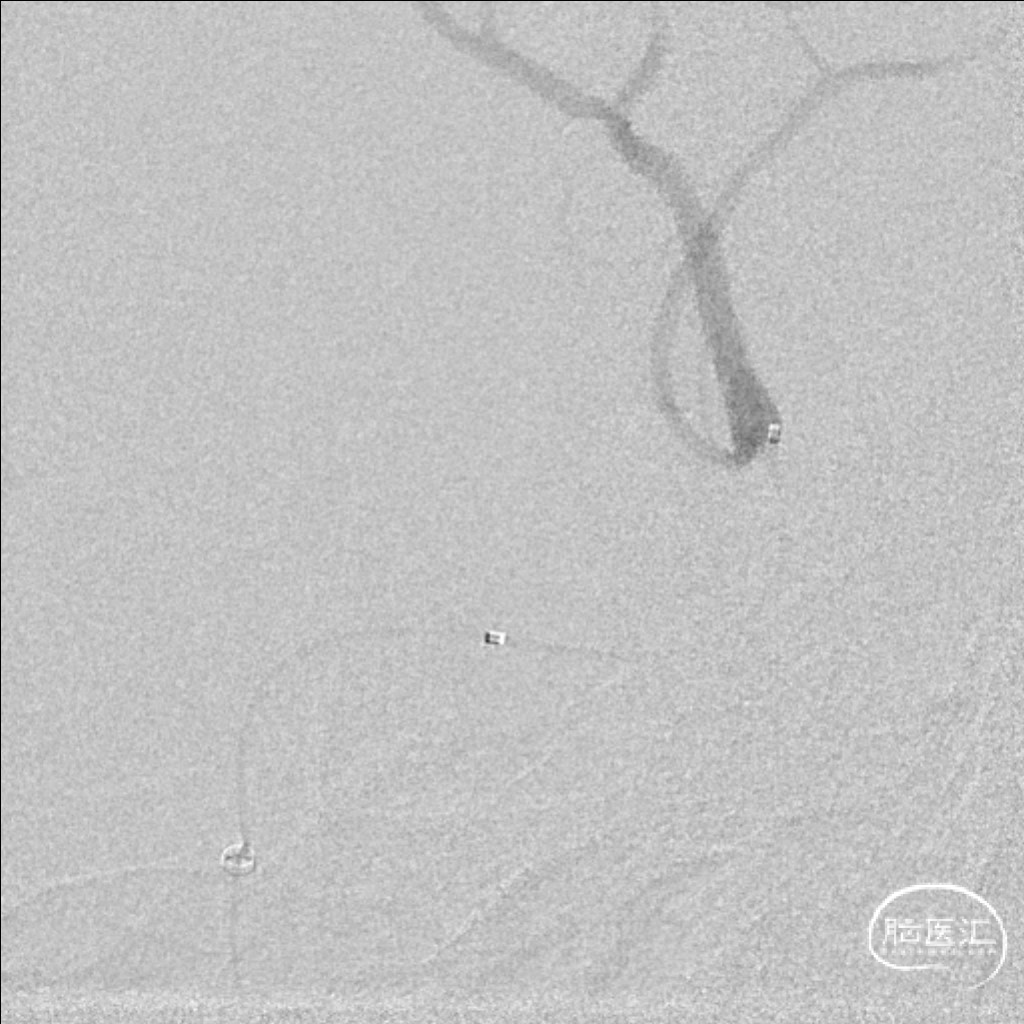

扩张后血管依然闭塞,改用2.0*15mm 球囊,扩张后提示M2段血流通畅,可见动脉瘤大小约4-5mm。

为尽快开通血管及处理动脉瘤,选择2.75*20mm 密网支架释放,并予以2.0*15mm 球囊后扩。

术后即刻影像,M2段远端血流mTICI 3级,动脉瘤内造影剂滞留。